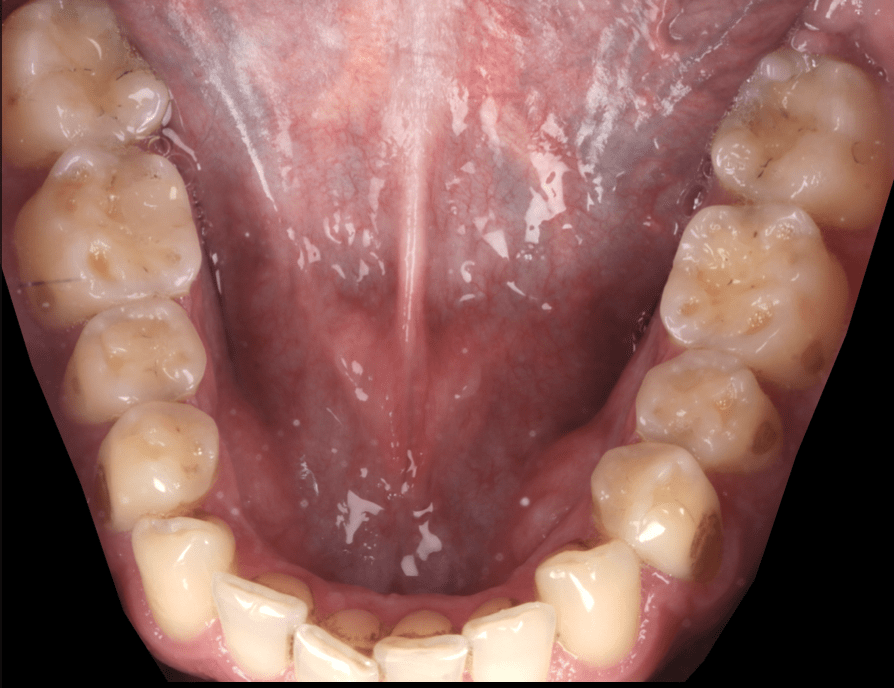

Avant/après d’un traitement interceptif de l’usure de la machoire du bas d’un de nos patients

Une réhabilitation d’une, voire des deux, arcades dentaires est souvent nécessaire pour préserver la fonction, et prévenir les dommages supplémentaires.

Elle repose sur l’utilisation de composites, un matériau dentaire qui imite l’aspect naturel des dents. Les composites sont appliqués directement sur les dents, sans avoir besoin de tailler ou de retirer des tissus dentaires sains. Cela permet de préserver la structure naturelle de vos dents tout en restaurant leur forme, leur fonction et leur esthétique. Cette approche est idéale pour protéger vos dents de manière peu invasive et empêcher la progression de l’usure.

Le traitement interceptif est une technique moderne et conservatrice utilisée pour traiter l’usure légère et modérée.